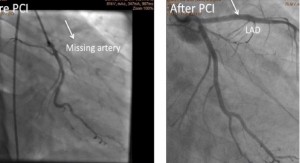

Chronic total occlusion angioplasty involves unblocking (or opening) the coronary artery that is completely occluded for more than a period of few months to many years. This is a challenging situation where there is no visualization of the pathway of the blood vessel to help pass wires and balloons. There are various special techniques available in these situations to open the blood vessel and perform stenting procedure. This can be achieved by opening the artery by direct pathway (antegrade approach) or through indirect pathway from the back of the artery (retrograde approach), using special kits (crossboss and stingray balloons) available in the cardiac catheter lab. This will help to improve the blood flow and make patient feel better. This procedure also needs special training to perform successfully as the success of the procedure comes with experience.